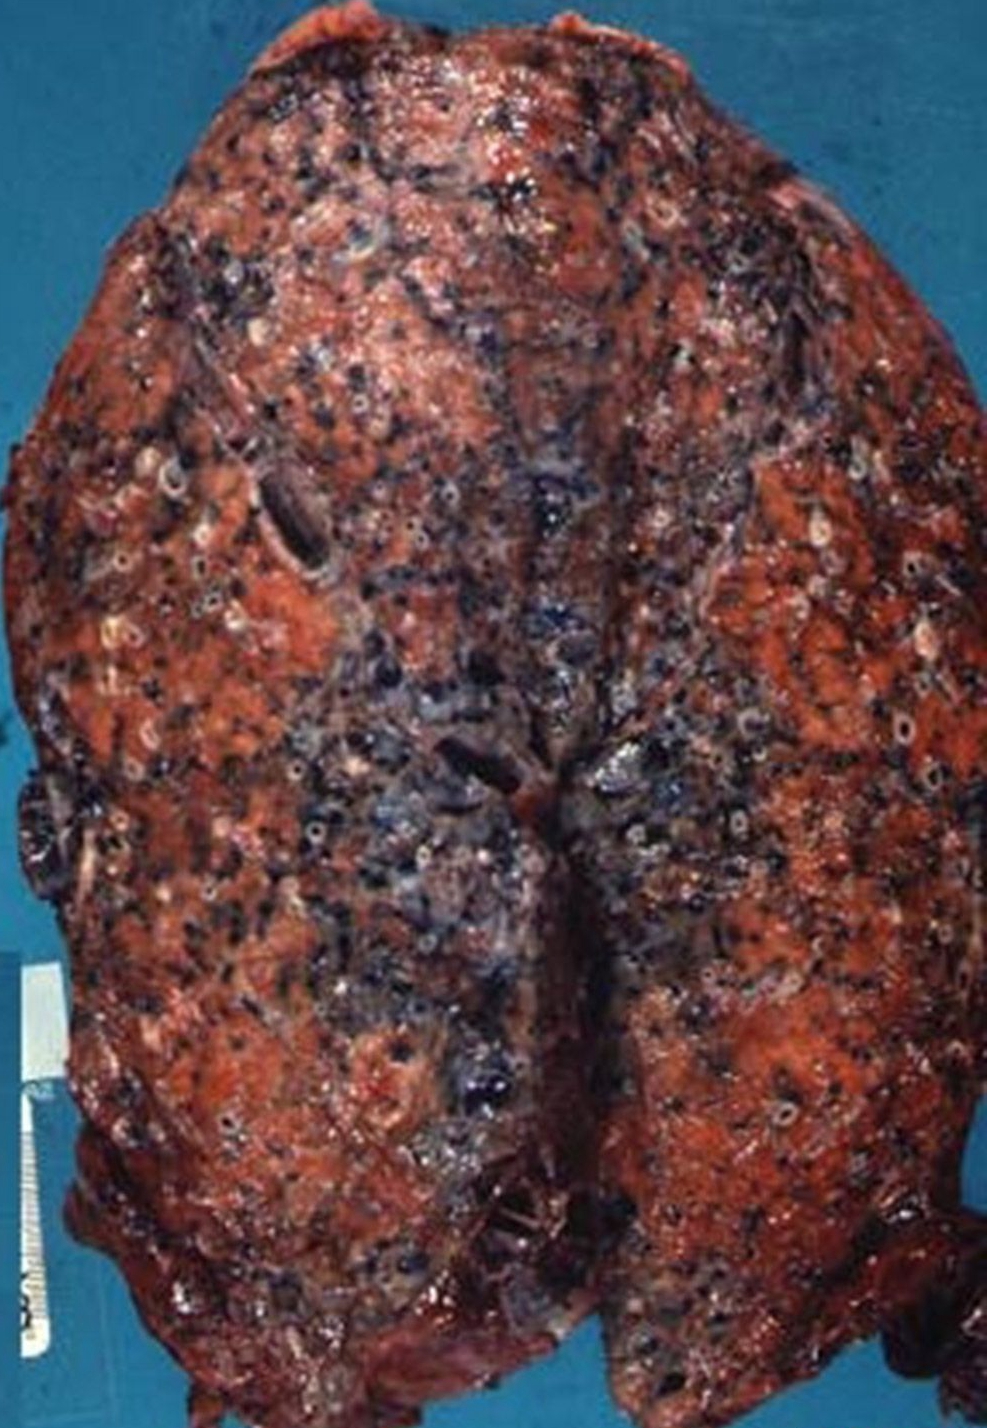

_原發性肺纖維化晚期

_重度肺纖維化的晚期

_重度肺纖維化晚期症狀